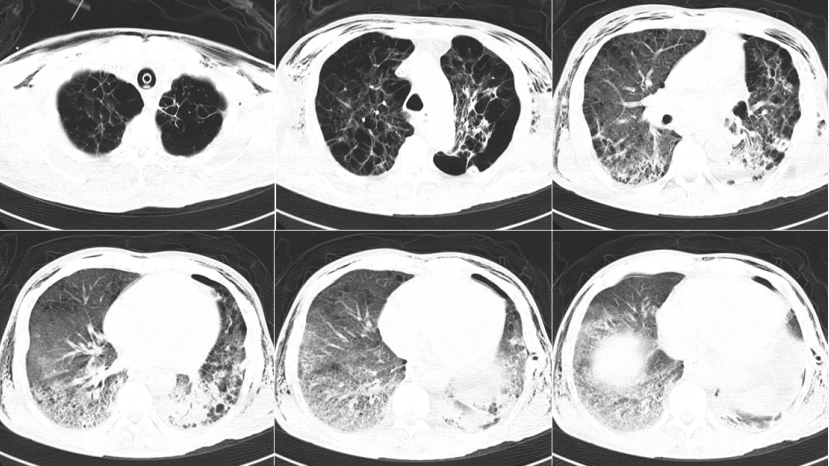

2024年3月3日BALF:鲍曼不动杆菌、白假丝酵母菌;PCT 7.614 ng/ml(↑),N-端脑利肭肽前体739.4 pg/ml。调整抗感染方案:多黏菌素E ivgtt+雾化、利奈唑胺、伏立康唑。3月3日复查胸部CT:左侧气胸,双层胸背部皮下气肿,双肺多发斑片影,左肺下叶切除术后,左侧少量胸腔积液,纵隔淋巴结肿大(图4)

4  复查胸部CT(2024-03-03)

3月10日复查胸部CT:左侧气胸,双层胸背部皮下气肿,双肺多发斑片影,双肺多发斑片影,左肺下叶切除术后,左侧少量胸腔积液,纵隔淋巴结肿大(图5)

5  复查胸部CT(2024-03-10)

3月31日复查胸部CT:双肺多发斑片影,左肺下叶切除术后,左侧少量胸腔积液,纵隔淋巴结肿大(图6)

6  复查胸部CT(2024-03-31)